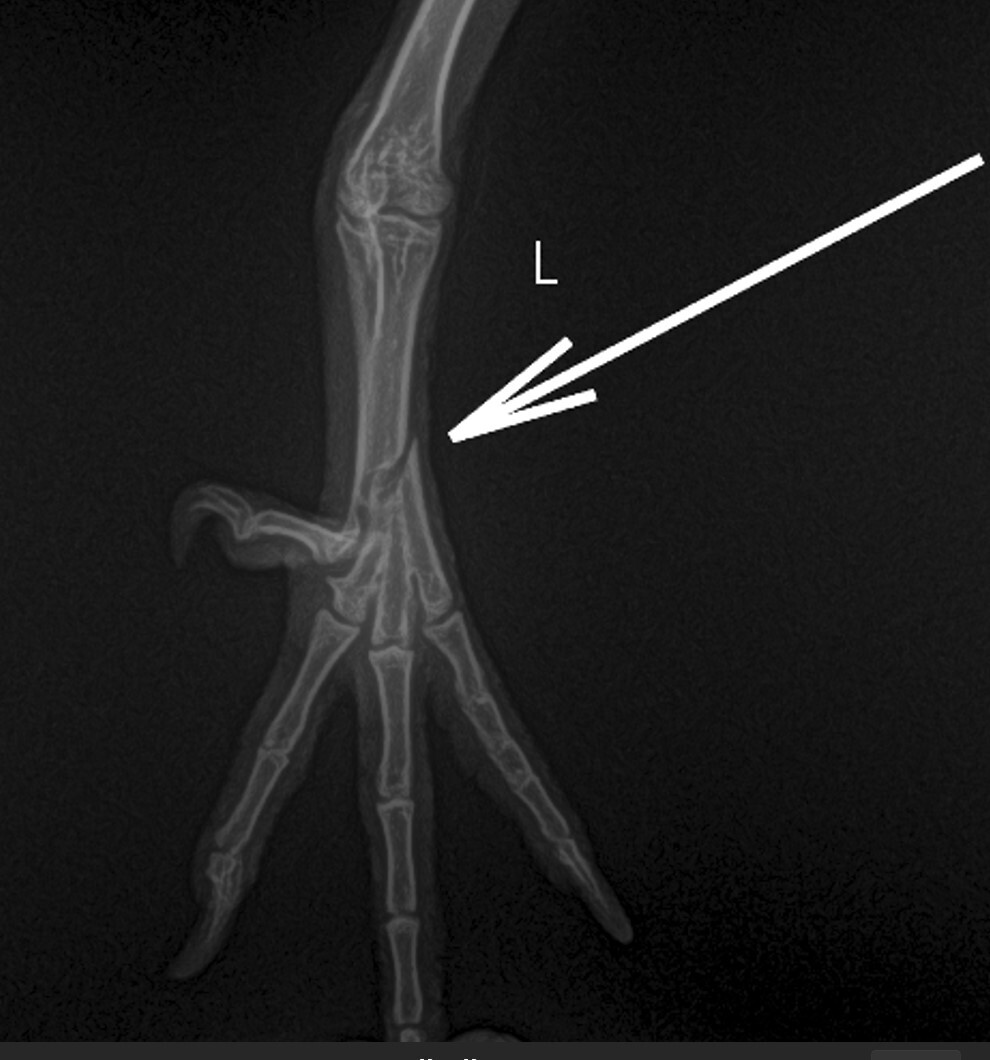

Голубь измучился и много очень выпил воды после "наложения" шины . На следующий день повёз к ветеринару, потому-что лапа начала чернеть (решил, что сепсис...). Ветеринар обрадовал, что это не сепсис, а зелёнка. Сказал что зелёнкой мазать нельзя голубю лапу - там каппиляры и тонкая кровеносняа система. И шину накладывать не надо было, сказал. Также сразу сказал, что сломано крыло. Сделали рентген. Предложил операцию за 10 тысяч, но результат 50/50. Денег не было, купил обезболивающее, антибиотик и оставил птицу на самореабилитации - без шины, без повязки на крыло. Только зелёную гречку давал, перловку. просо, пшеницу, камень минеральный для птицы, витамины, и немного обезболивающего и антибиотиков вначале.